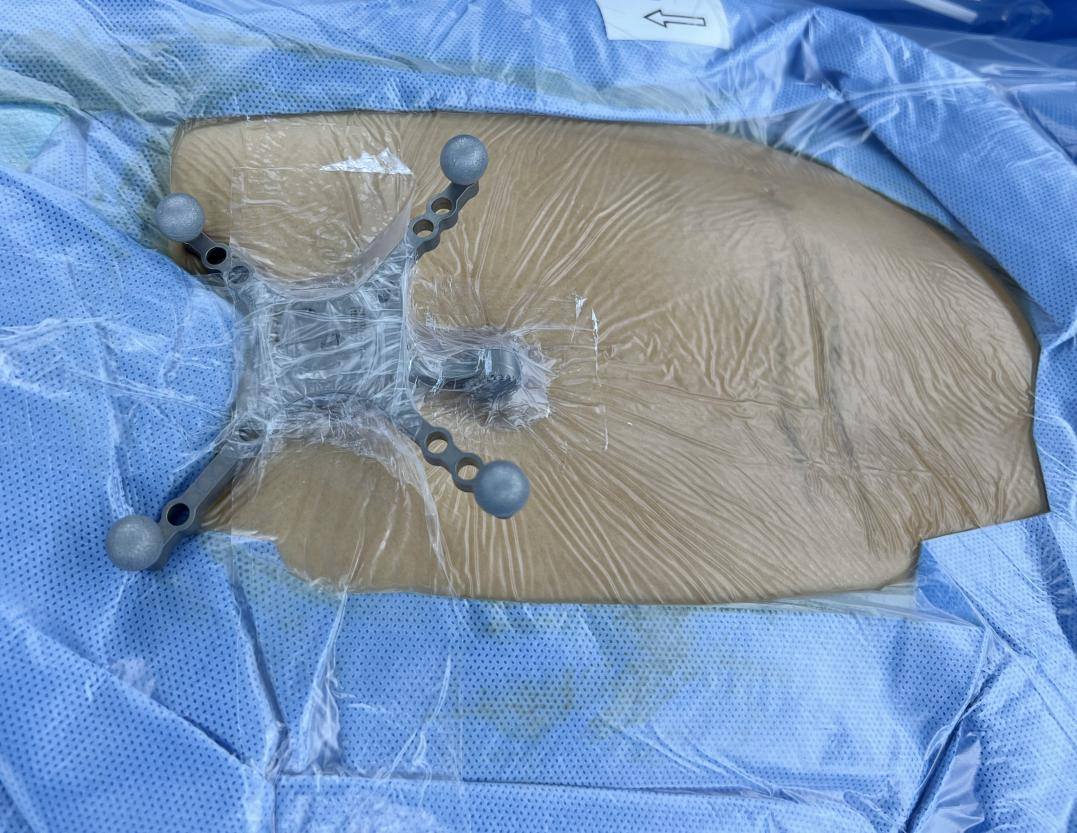

肌电监测及S8导航辅助完成手术

“尽早解除脊髓神经压迫不仅能缓解患者症状,更是为了避免压迫时间太长影响恢复,甚至导致功能障碍!”杨俊松副主任医师说。为了保证安全性,手术全程在肌电监测及S8导航下完成。

术中资料

手术中,杨俊松副主任医师在术中影像科的密切配合下采用S8导航进行了实时的操作导引,给手术插上了“透视眼”。为增加手术安全性,采用超声骨刀仔细去除钙化物,给受压的脊髓神经减压,影像显示减压彻底。